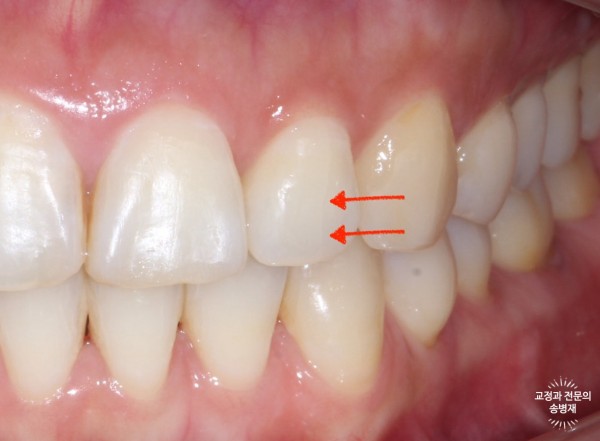

위에서 빨간 화살표로 표시한 실금이 잘 보이시나요?

치아에서 보이는 실금은 craze line이라고 부르며, 치아 표면 약 0.1mm 내의 야주 얕은 깊이의 실금입니다.

이러한 실금은 훨씬 더 깊이 금이 간 치아파절(crack line)과 구별됩니다.

아래는 치아파절인 경우입니다.

치아가 파절된 경우 위 그림과 같이 그 선이 훨씬 선명하게 보이는 경우가 있으며(시간이 지난 경우 착색되기 때문)

통증이나 염증이 수반되는 경우가 많기 때문에 발치해야 하는 경우가 많습니다.